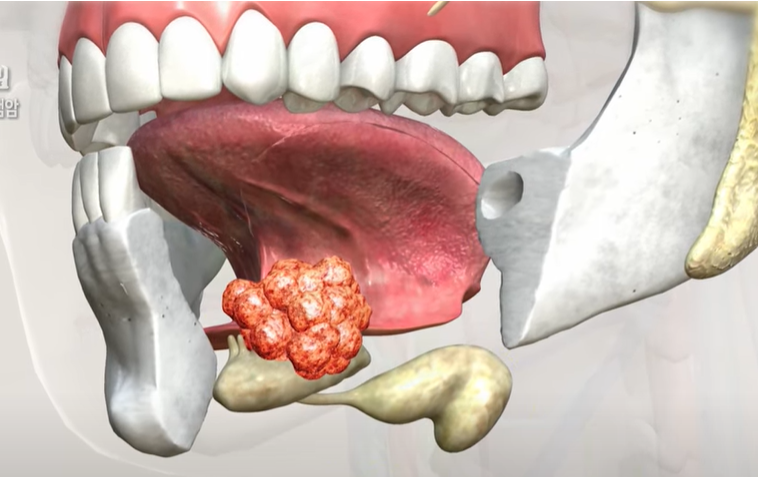

침샘은 구강 내에서 침을 분비하는 기관으로, 크게 귀밑샘(이하선), 턱밑샘(악하선), 혀밑샘(설하선)으로 나뉘며, 더 작은 침샘들(부타액선)도 존재합니다.

침샘종양은 이러한 침샘에서 발생하는 종양으로, 대다수는 귀밑샘에서 시작됩니다. 조직학적으로 매우 다양한 유형이 존재하며, 성질 및 위치에 따라 암의 진행 정도와 치료 반응이 다르기 때문에 개별화된 접근이 필요합니다.

침샘암의 치료는 종괴를 완벽하게 제거하는 것이 가장 핵심이며, 치료법은 종양의 크기와 위치, 악성도에 따라 달라집니다.

침샘 종양 제거 수술은 가장 기본적인 치료이며, 암의 크기에 따라 추가 절제가 필요할 수 있습니다.